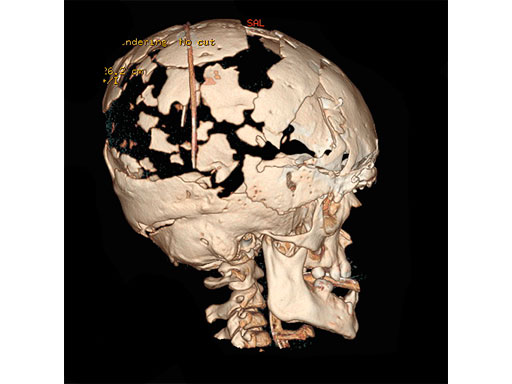

An 8-year-old girl with Apert Syndrome (Fig 5) was examined after being treated at another institution. The cause for loss of cranial bone was unknown. An anterior and posterior cranial expansion was given to treat the increased intracranial pressure.

After that healed, a simultaneous PSI cranioplasty and Le fort II osteotomy with zygoma repositioning were performed. The PEEK implants were fixated using MatrixNeuro ULP implants (Fig 6). A midface distraction device was then mounted on the PSI implants and distracted the Lefort 2 segment to treat the patient's sleep apnea (Fig 7).

Case provided by Richard Hopper, Seattle, USA.